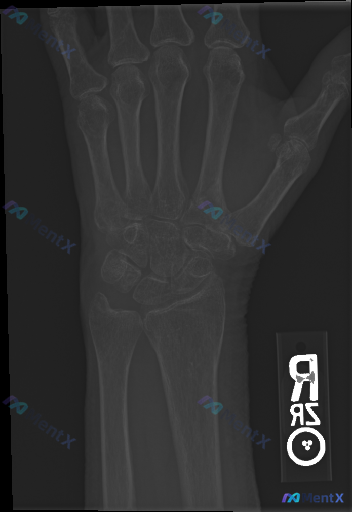

整理到一份右侧手腕及手部正位X光片的影像资料,先把主要的影像表现整理出来,大家看看这种情况会怎么判断? 影像表现概要 - 骨骼完整性:腕骨、掌骨及尺桡骨远端骨皮质连续,未见明确骨折线或骨折断端;骨小梁排列清晰,未见紊乱、压缩或塌陷征象。 - 关节关系:腕骨排列良好,Gilula弧线走行自然、连续,未...